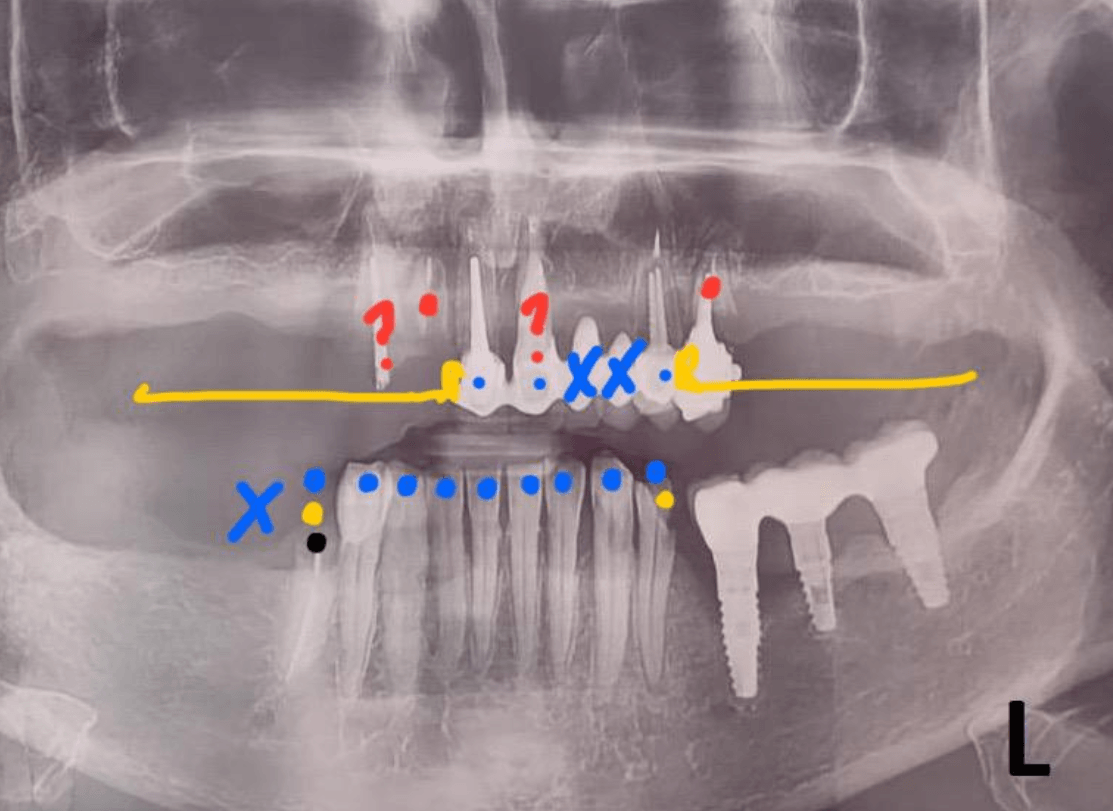

Врач вручную выделяет проблемные зоны цветами, ставит символы-маркеры, пишет комментарии.

Компьютерное зрение вместо рутинной работы врача. Наша модель сама размечает снимок, подсвечивает проблемные зоны привычными цветами и символами, формирует предварительный диагноз и передаёт кейс менеджеру. Врач из рутинной части процесса исключён и занят тем, где незаменим — клиническими задачами и очным приёмом.

Запуск ML-инференса и сохранение разметки (цвета/символы, преддиагноз).